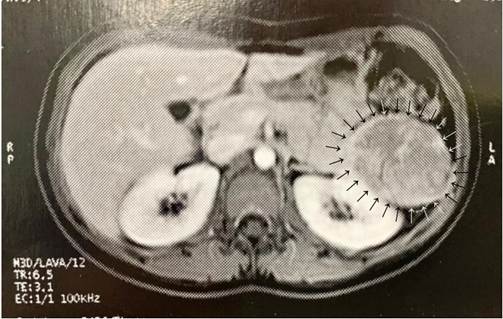

Uma jovem assintomática realizou aos 13 anos ultrassonografia abdominal em rotina de exames, sendo evidenciada, conforme laudo, “imagem arredondada de 4,2 x 3,3 centímetros (cm), com ecotextura semelhante ao baço, em íntimo contato com este órgão, podendo representar baço acessório”. Um ano depois, uma nova ultrassonografia foi realizada, revelando aumento da lesão (5,9 x 5,4 cm), sendo sugerida correlação com ressonância nuclear magnética (RNM). A RNM de abdome superior com contraste identificou formação expansiva heterogênea bem delimitada, com predomínio de alto sinal em T2 e focos hemáticos de permeio, localizada junto à cauda pancreática, com insinuação ao hilo esplênico, apresentando áreas de aparente realce, medindo 6,4 x 5,4 cm (Figura 1), sendo aventada hipótese de tumor de Frantz.

Figura 1. Ressonância nuclear magnética de abdômen (setas pretas/cinzas: neoplasia sólida pseudopapilar do pâncreas)